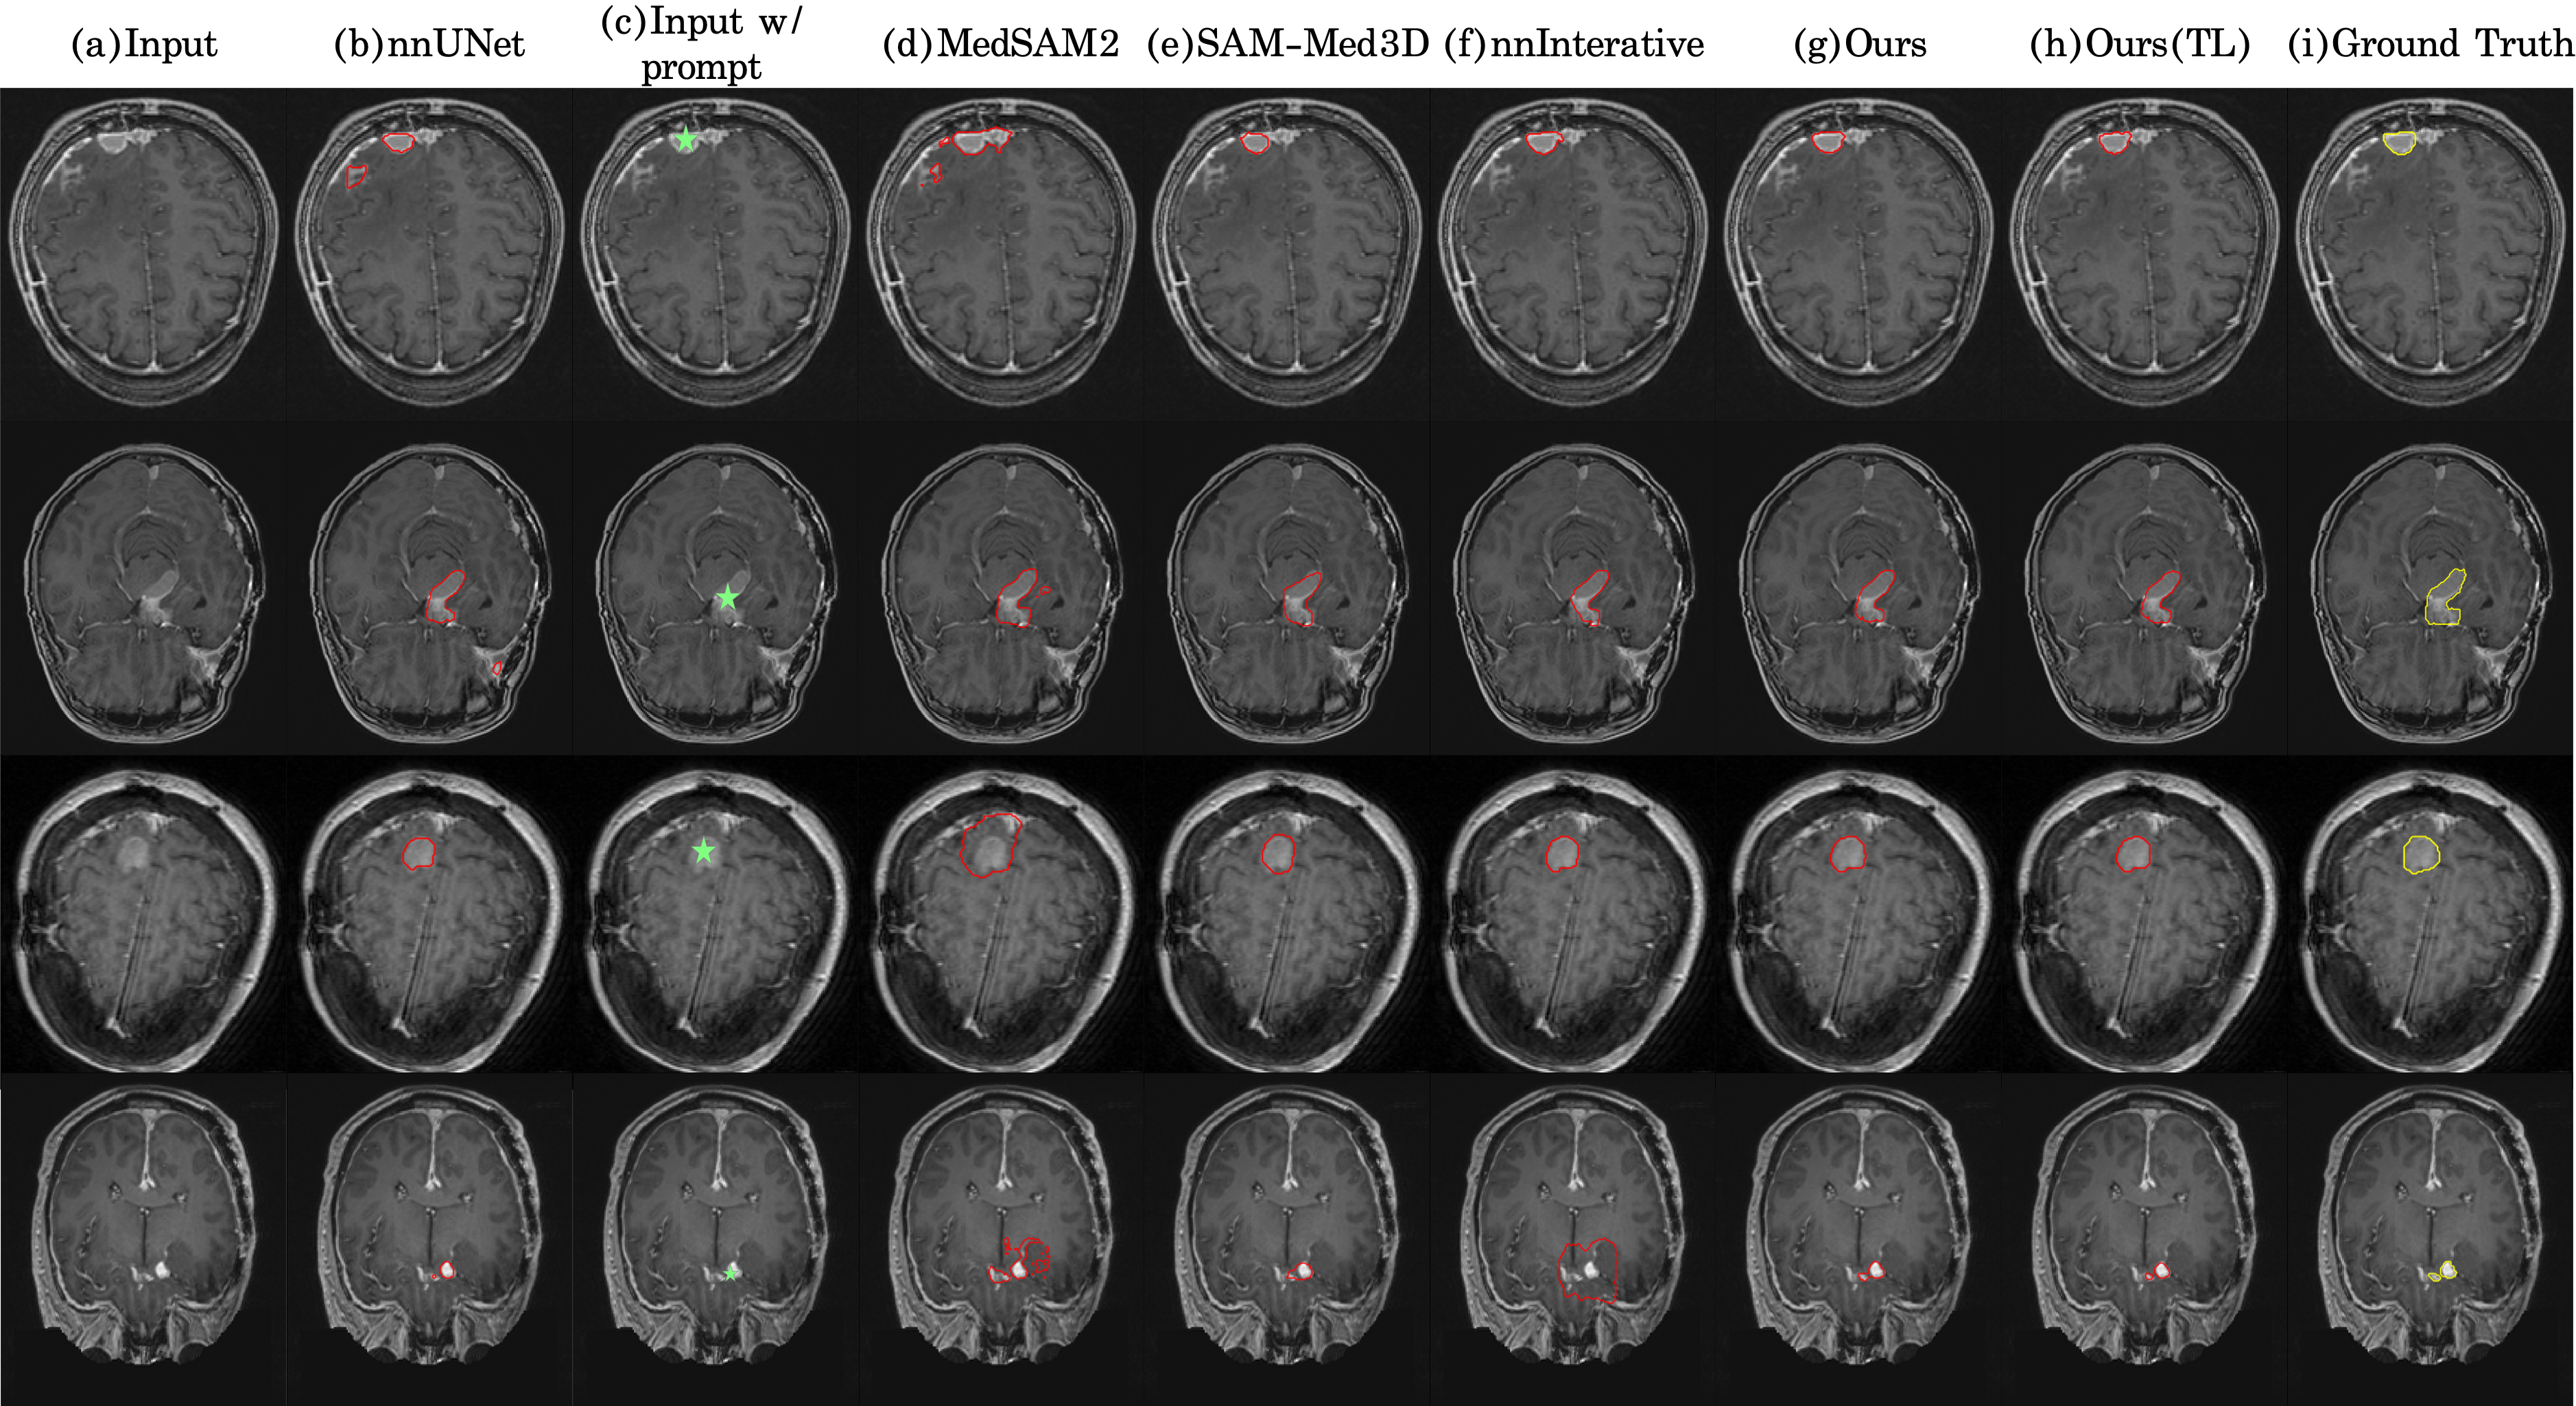

Refer to caption

Figure 3: Qualitative segmentation overlays for each method and the ground truth under point prompt interaction settings.

3.3 Comparative Qualitative Analysis of Segmentation Methods

Fig. 3 presents a qualitative comparison of segmentation results obtained under a single point prompt on representative meningioma cases. The figure facilitates a direct visual comparison of outputs from MedSAM2, SAM-Med3D, nnInteractive, Interactive-MEN-RT (trained from scratch), and Interactive-MEN-RT (with transfer learning) against the ground truth annotations. Each row corresponds to a distinct meningioma case, strategically chosen to exemplify the diversity of tumor locations relevant to RT planning: convexity, skull base, falx/parasagittal, and ventricular regions. This presentation of qualitative results across varied clinical scenarios effectively demonstrates the robustness and adaptability of Interactive-MEN-RT.